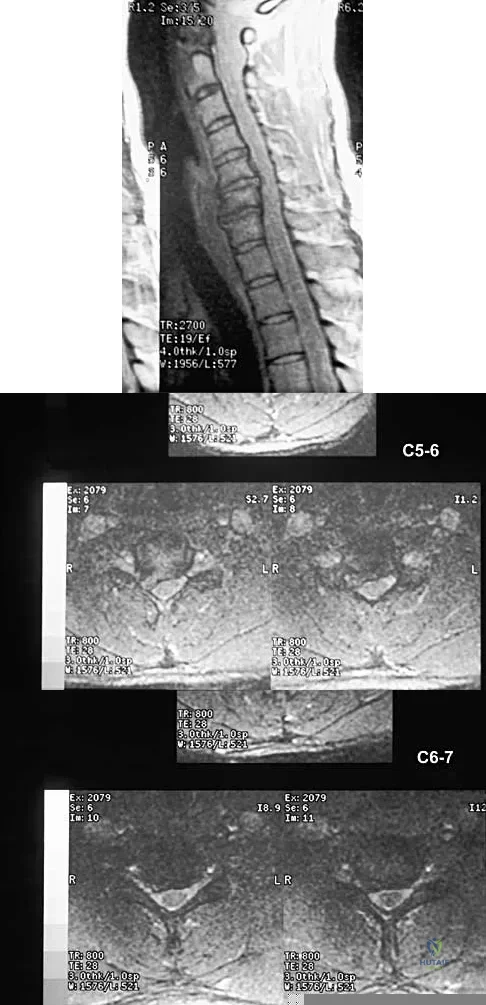

A 40-year-old carpenter has a 3-month history of right arm pain and neck pain that now leaves him unable to work. Examination reveals a positive Spurling test, weakness of the biceps, and a mildly positive Hoffman's sign on the right side. Electromyography and nerve conduction velocity studies show a right C6 deficit. Figures 27a through 27c show MRI scans that reveal two-level spondylotic disease at C5-6 and C6-7, a large herniated nucleus pulposus at C5-6, and a prominent ridge and hard disk at C6-7. Nonsurgical management fails to provide relief, so the patient elects surgical intervention. Which of the following surgical options would give the best long-term results?

Explanation